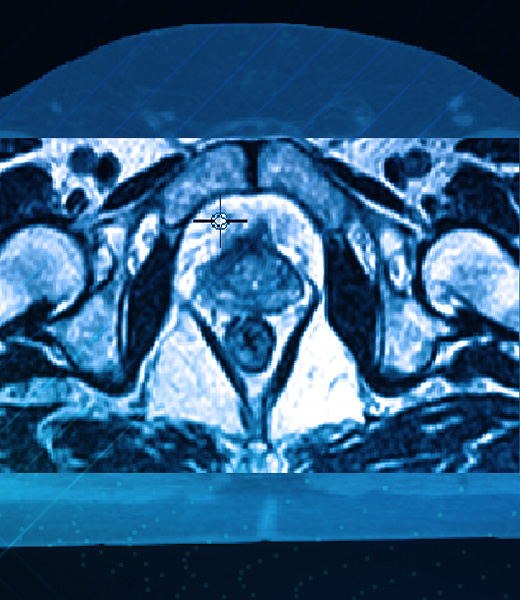

Para la planificacion este sistema permite la incorporacion de metodos complementarios de imagenes, siendo la base la Tomografia Axial. Estas imagenes pueden fusionarse con imagenes de Resonancia Magnetica y/o Tomografia por emision de positrones (PET), permitiendo al medico pasar de un conjunto a otro de imagenes de manera continua para seleccionar la mejor visualizacion tanto del blanco como de otras estructuras de interes.